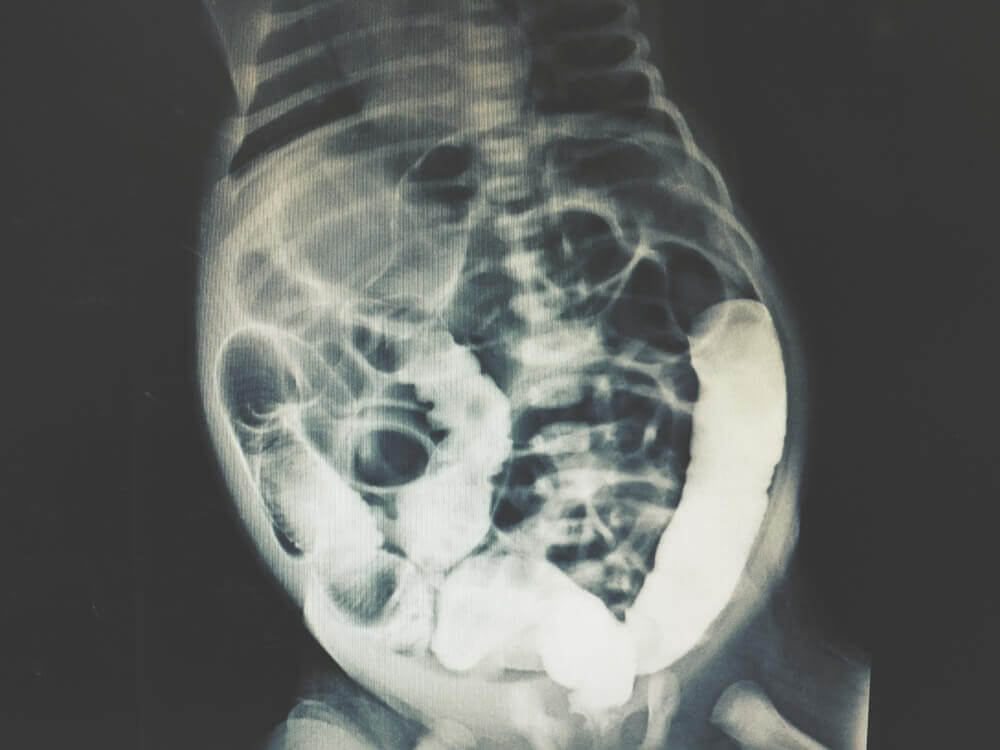

Actuellement, il s’agit d’un test médical très fiable qui produit un nombre minimum de faux positifs ou d’autres erreurs. De plus, on l’utilise conjointement avec d’autres outils diagnostics de l’imagerie. C’est le cas de la tomodensitométrie (tomographie axiale informatisée) ou de l’IRM (imagerie par résonance magnétique).

En fonction des résultats obtenus, le groupe d’experts peut déterminer la cause de l’altération abdominale. On peut également effectuer des tests pour obtenir des images internes de la région abdominale afin de faciliter le diagnostic.